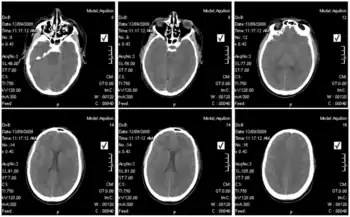

Lujo hemorrhagic fever- CT scan of the brain of infected individual showing cerebral edema

Blood tests of those infected revealed elevated liver values, white blood cell counts that were first low and then elevated over time, and low platelet counts.[8]In terms of the diagnosis of Lujo hemorrhagic fever the following is done:[15][16]